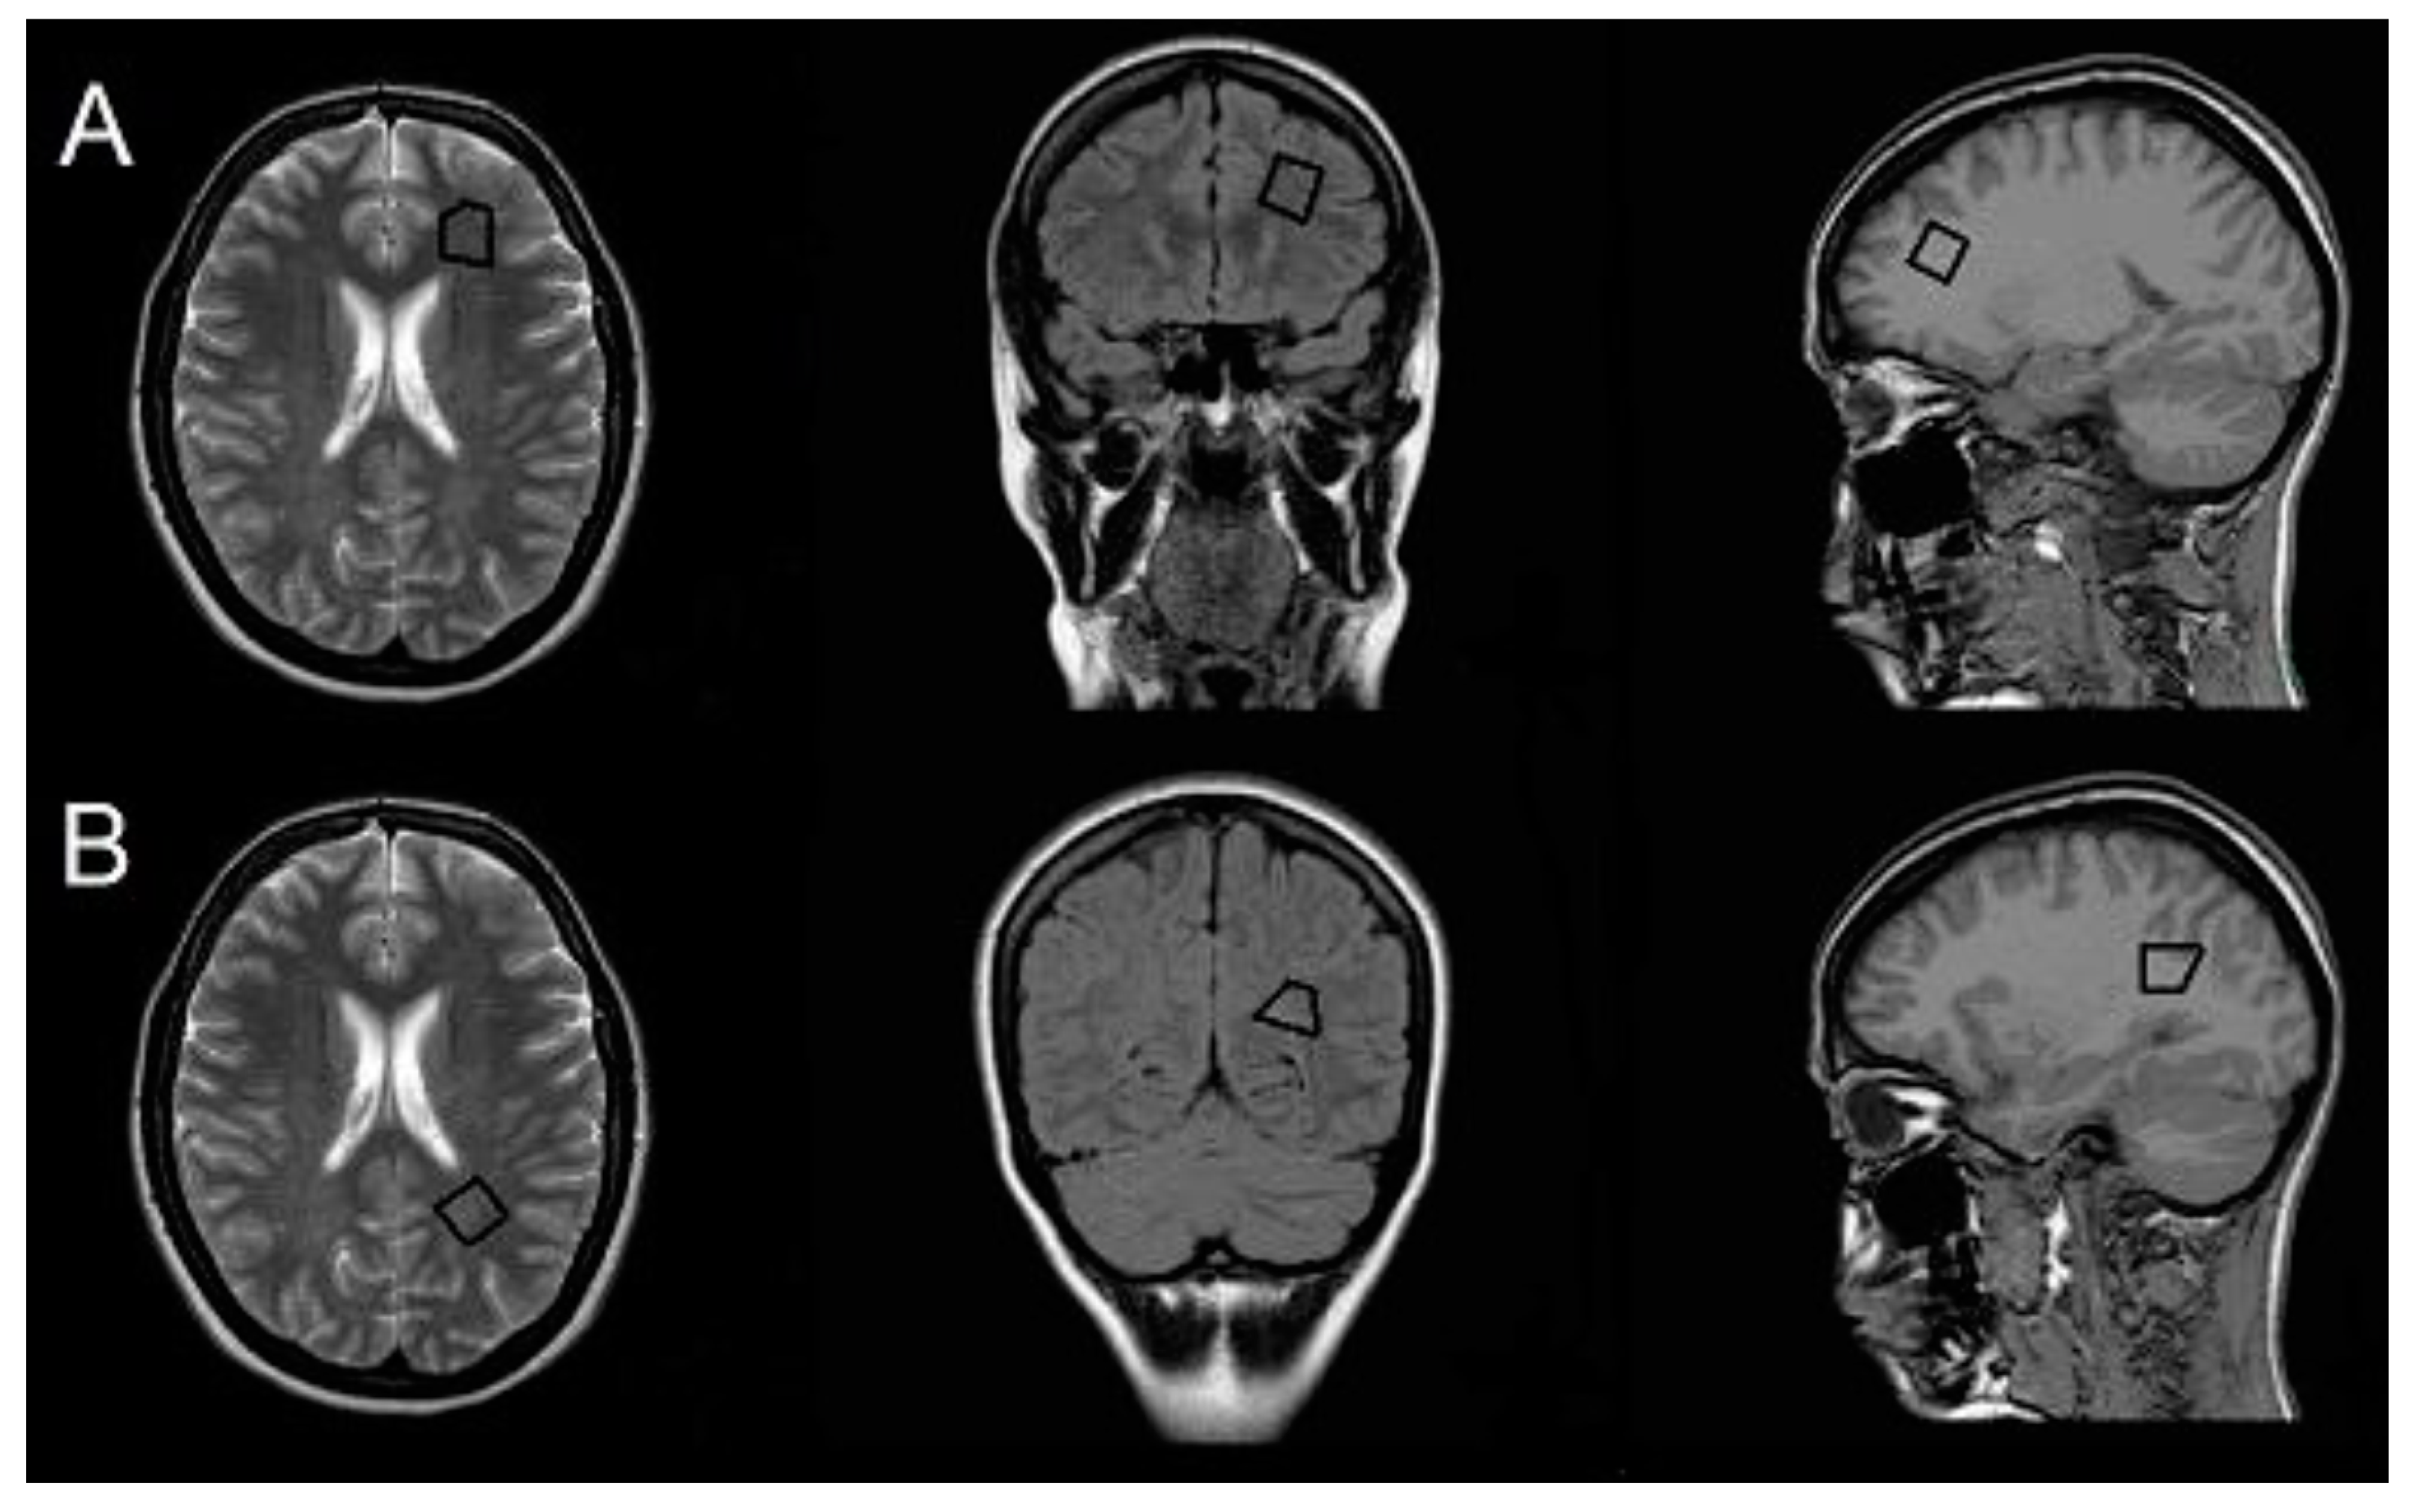

1H-MRS was acquired at the same time as conventional MRI with the same scanner before the gadolinium-based contrast agent was administered. For planning and locating the target voxel, the following scans were acquired: transverse T2 TSE (TR, 4847 ms; TE, 100 ms; ST, 5 mm), axial T1 (TR, 135 ms; TE, 1.79 ms; ST, 5 mm), and coronal FLAIR (TR, 600 ms; TE, 120 ms; inversion time, 2000 ms). Then, a single-voxel 1H-MRS was acquired for the following two volumes of interest (VOIs; 2.7 mL) in NAWM in the left hemisphere: (i) the frontal region anterolaterally to the frontal horn of the lateral ventricle; and (ii) the parietal region superolateral to the trigone of the lateral ventricle (Figure 1). The VOI was defined manually using scans in the transverse, axial, and coronal planes to maximize the area of NAWM sampled while excluding cerebrospinal fluid, gray matter, and demyelinated lesions. In cases where the VOI could not be placed in the left hemisphere because of lesions, the right hemisphere was chosen as there is no evidence for hemispheric differences in the NAWM 1H-MRS measures [,]. A point-resolved spectroscopy sequence with TR of 2000 ms and TE of 31 and 144 ms was used in the 1H-MRS acquisition. Water was suppressed with the chemical shift selective saturation technique (CHESS). Water suppression and shimming were optimized automatically. A medical physicist experienced in 1H-MRS analysis performed postprocessing with SpectroView software (Philips). We semi-quantitatively assessed metabolite concentrations by calculating relative peak area ratios for N-acetyl-aspartate (NAA)/creatine (Cr) and NAA/choline (Cho) for long TE (144 ms) and Cho/Cr, myo-inositol (mI)/Cr, and NAA/mI for short TE (31 ms).

Figure 1.

Volume of interest. Positions of volumes of interest (VOIs) in normal-appearing white matter (NAWM) in frontal (A) and parietal (B) regions.